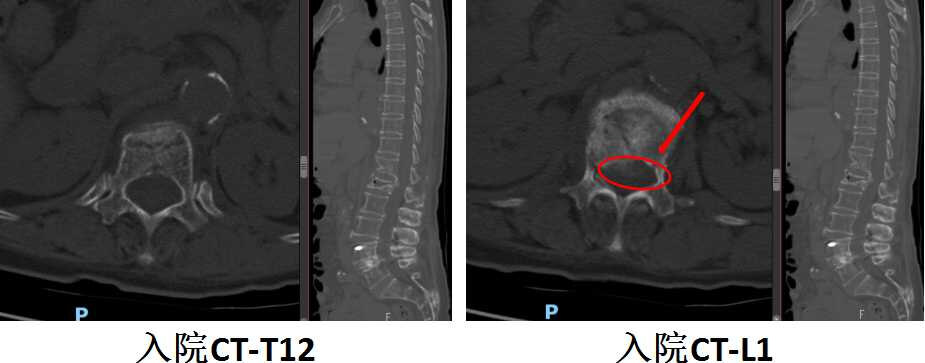

陈奶奶骨折后CT结果,示骨折压迫脊髓

陈奶奶骨折后MRI结果,示骨折部位以及脊髓压迫

看这个MRI和CT的结果,T12和L1这两个地方的压缩性骨折肯定没跑了,但是这个骨折有一小部分压迫到了脊髓和神经,失去了打骨水泥这种微创手术的机会。不得不做了一个大的开放性的后路T12、L1椎体骨折切开复位内固定术。又给加了5对也就是10个钉子在里面。